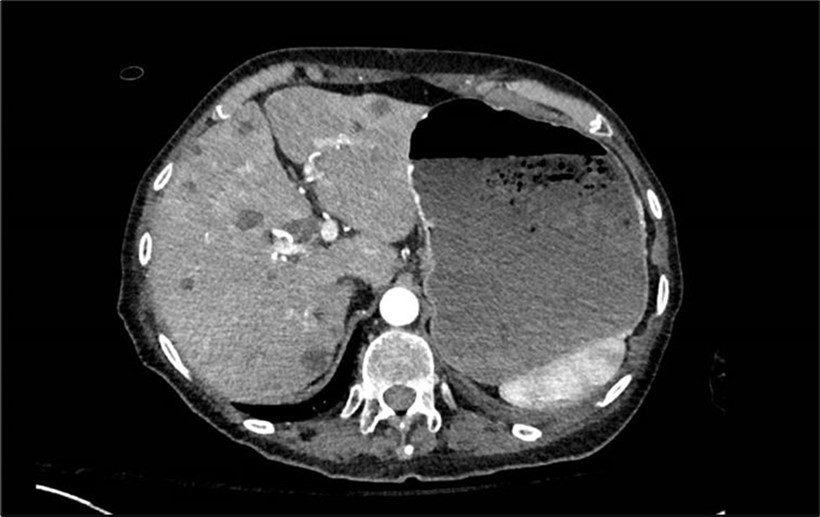

A right upper quadrant ultrasound showed a hypoechoic lesion in the head of the pancreas measuring 3.1 cm, associated with dilation of the main pancreatic and common bile duct. The liver appearance was heterogeneous with focal hypodense lesions. Further blood work was remarkable for a carcinoembryonic antigen of 2139 ng/mL and cancer antigen 19-9 was, 11782 U/mL. A CT chest, abdomen, and pelvis with contrast showed a 3.4x2.5 cm pancreatic head mass invading the duodenum, occlusive thrombi of the main portal vein and superior mesenteric vein, multiple liver lesions, and a distended stomach concerning for partial gastric outlet obstruction (Image 2). The diagnosis of pancreatic adenocarcinoma was confirmed via biopsy.

Image 2.CT scan showing liver with multiple metastatic lesions and a large stomach